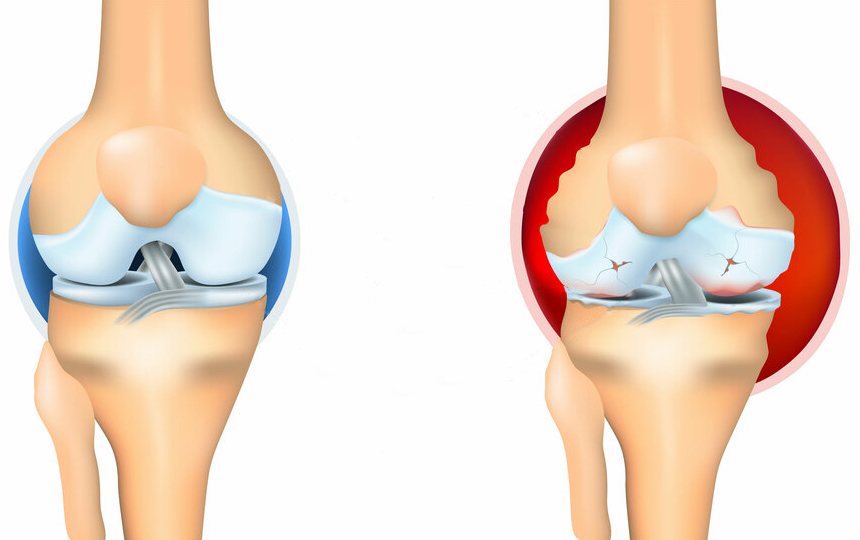

อาการปวดเป็นสัญญาณสำคัญที่บ่งชี้ว่ามีความผิดปกติในข้อ การแค่ทำให้หายปวดจะทำให้สภาพของข้อต่อแย่ลง กระบวนการเสื่อมสภาพจะเร็วขึ้น 3-5 เท่า ส่งผลให้เกิดการเปลี่ยนแปลงที่ย้อนกลับไม่ได้ สูญเสียการเคลื่อนไหวและนำไปสู่การพิการในที่สุด

เมื่อเกลือเหล่านี้เกาะอยู่บนพื้นผิวของข้อต่อ คราบเกลือเหล่านี้เหมือนกระดาษทรายที่ทำลายเนื้อเยื่อรอบโดยรอบ กระดูก และกระดูกอ่อน เมื่อผลึกโตขึ้น เกลือจะเริ่มทำลายเนื้อเยื่อของกล้ามเนื้อ เอ็น หลอดเลือด และเส้นเลือดฝอย ทำให้เกิดการอักเสบ ติดเชื้อ บวม ก่อให้เกิดการอักเสบและปวดอย่างรุนแรง

ในความเป็นจริงแล้ว ข้อต่อมนุษย์มีความสามารถในการฟื้นฟูตัวเองสูงมาก ข้อต่อเหล่านี้สามารถฟื้นฟูตัวเองได้เช่นเดียวกับหางของกิ้งก่า เพียงแค่ต้องได้รับความช่วยเหลือเล็กน้อย แค่ต้องเอาเกลือที่เกาะอยู่ออก แล้วกระบวนการฟื้นฟูก็จะเริ่มขึ้น